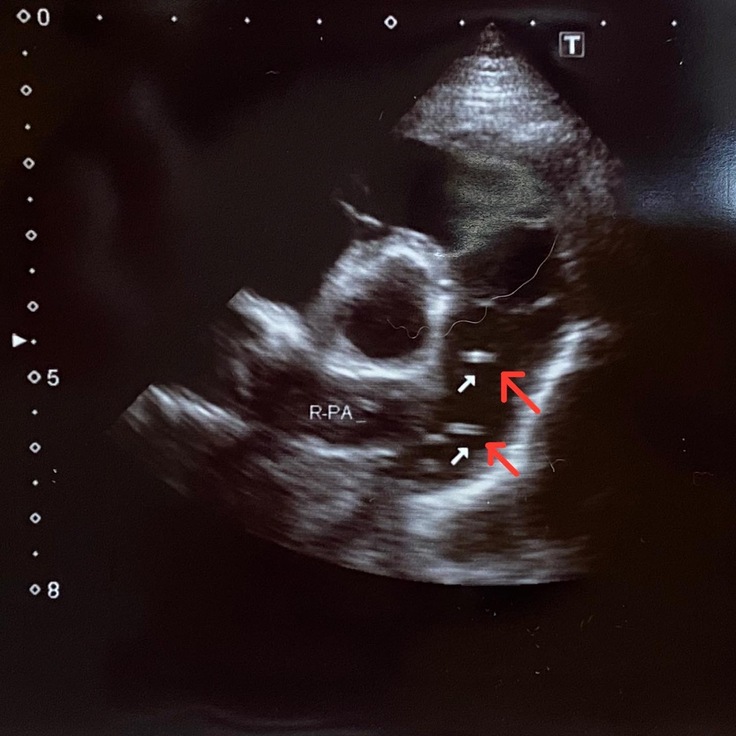

エコー写真を見て発覚したのは、フィラリア成虫が右心房から右心室に流れる間にある弁(三尖弁)に大量に絡みついており、弁がしっかり閉じられていないという状態になっていました。

↓黒いペンで書かれた矢印の先にある、白いグチャグチャに集まったものがフィラリア成虫です

そして、右心房から右心室に流れる度に閉じなければならない三尖弁が閉じない

血液の80%は流れるけど20%は右心房に逆流する

でも右心房には次に流れてくる100%の血液が待ち構えている

逆流した20%と100%の血液を合わせて、毎回120%のポンプ運動で心臓が動いている

そのせいで、本来あるべき心臓のサイズから考えられないくらい変わってしまい、かなり圧迫している状態になってしまっているとのことでした。